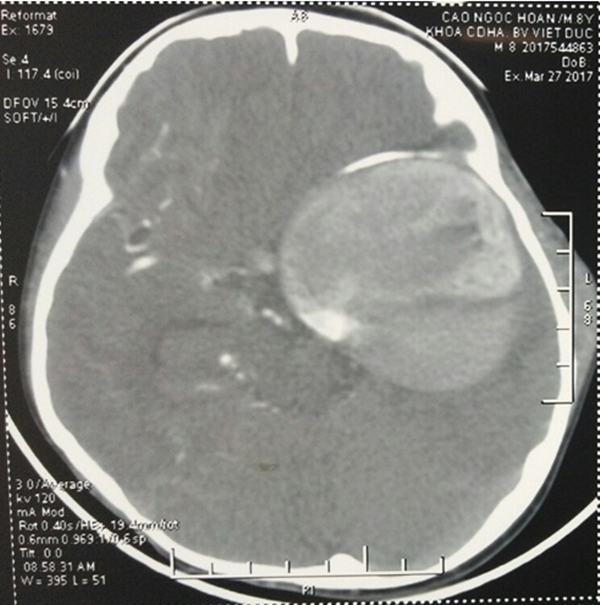

Phim chụp triệu chứng của bệnh nhân 8 tuổi.

Theo đó, bệnh nhân 8 tuổi nhập viện ngày 3/6/2017 trong tình trạng bị phình động mạch cảnh trong khổng lồ, kích thước 10 x 12cm, đây là một trường hợp hiếm gặp trong y học. Bình thường phình động mạch cảnh trong có kích thước >1,5cm là lớn, > 2,5 cm là khổng lồ.

Đối với bệnh nhân H., khối phình mạch nằm ở hố thái dương gây chèn ép trực tiếp vào các dây thần kinh của mạch máu nền sọ và gây ra hiệu ứng khối nên bệnh nhân sẽ có các triệu chứng do tăng áp lực hộp sọ bởi khối phình mạch khổng lồ và những biểu hiện do khối phình mạch chèn ép trực tiếp vào các dây thần kinh mạch máu nền sọ. Bệnh nhân H bị khối phình mạch đã chèn ép trực tiếp vào dây thần kinh thị giác khiến bệnh nhân bị mất thị lực hoàn toàn.

Bệnh nhân đã mất thị lực mắt trái nhiều năm và trong vòng 1 tháng thị lực mắt phải đã giảm sút, hiện tại mắt phải chỉ nhìn đếm ngón tay. Ngoài khối phình mạch khổng lồ của động mạch cảnh trong, bệnh nhân còn có nhiều khối phình mạch trên cơ thể như phình ở động mạch dưới đòn phải, ở động mạch thận trái, động mạch cánh tay phải. Nếu không được can thiệp kịp thời bé có nguy cơ cao tử vong.